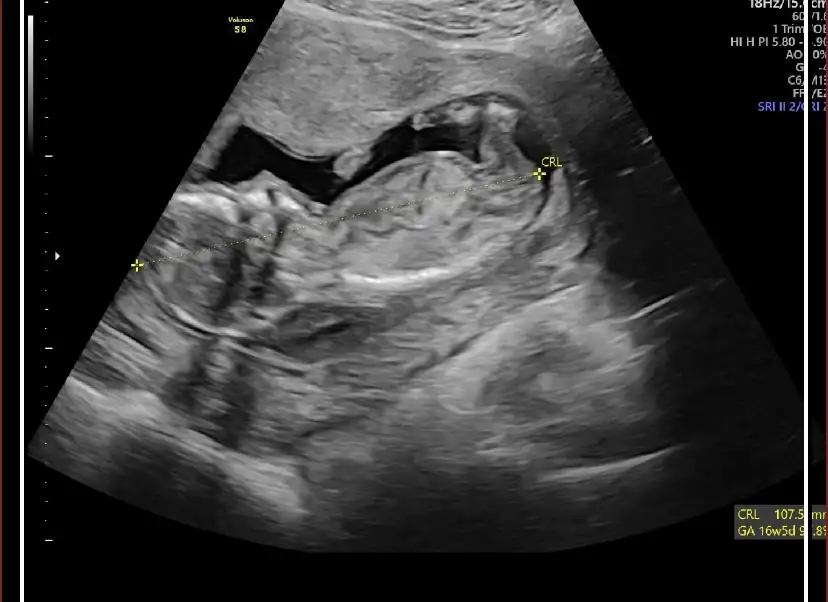

nerden başlasam bilemiyorum o kadar aklım karışıkki ne yapacağımı bilemiyorum lütfen fikirlerinizi yazın. son adet tarifime göre 15 haftalık hamileyim bebeğin kalp atışını duyana kadar günü tutuyordu. sonra 12 haftalıkken kontrole gittim gününden sapmış hastalıklı bir bebek olma ihtimalinin olduğunu söyledi doktor başka doktorada göründüm oda perinatolojiye yönlemdirdi.2 gün önce gittim.15 haftalık gebeliğim,16+5 olarak gözüküyordu. doktor o kadar şey saydıki bebeğin yaşama ihtimali yok dedim ama doktor doğabileceğini ama doğsa bile yaşama ihtimalinin çok düşük olduğunu söyledi.ense kalınlığı ve burun kemiğinin küçük oluşundan down sendromlu olduğunu. iki bacağınında eğri ve kısa olduğunu. iki böbreğininde çalışamaz durumda olduğu için vücudunun su topladığını böbreklerinin iflas ettiğini ve karnında oluşan fıtıktan dolayı karaciğer ve bağırsaklarının dışarda olduğunu söyledi. böylelikle dünyam başıma yıkıldı sonlandırmak gerektiğini ve bunun günah olmadığını söyledi doktor. öyle bir durumdaydımki sonlandırmak bile benim için umuttu ama diyanet danışma hattını aradım bana bebek karnımda olduğu sürece bana zarar verme riski bulunmadıkça günah olduğunu söyledi. bebeğin kalbinde bir sıkıntı yok yaşar diye korkar mı bir anne kendimi çok kötü hissediyorum ölmesini istediğim için. ama doktor yaşarsada zihinende bedenende ileri derece özürlü olacağını tuvalete bile gidemeyeceğini söyledi hem onun için hem bizim için çok zor bir süreç olduğunu yaşlarımızında daha çok genç olduğunu sonlandırmak gerektiğini söyledi.sonlandırırsam ilerde daha kötüsü gelir başıma diye korkuyorum zaten bugüne kadar ne konuşursam başıma bela olarak tekrar karşıma çıkıyor elim kolum bağlı bir durumda amniyosentez testimin sonucunu bekliyorum.aşağı bebeğin bir kaç görüntüsünü bırakacam ben pek bir şey anlamasamda belki siz anlarsınız.